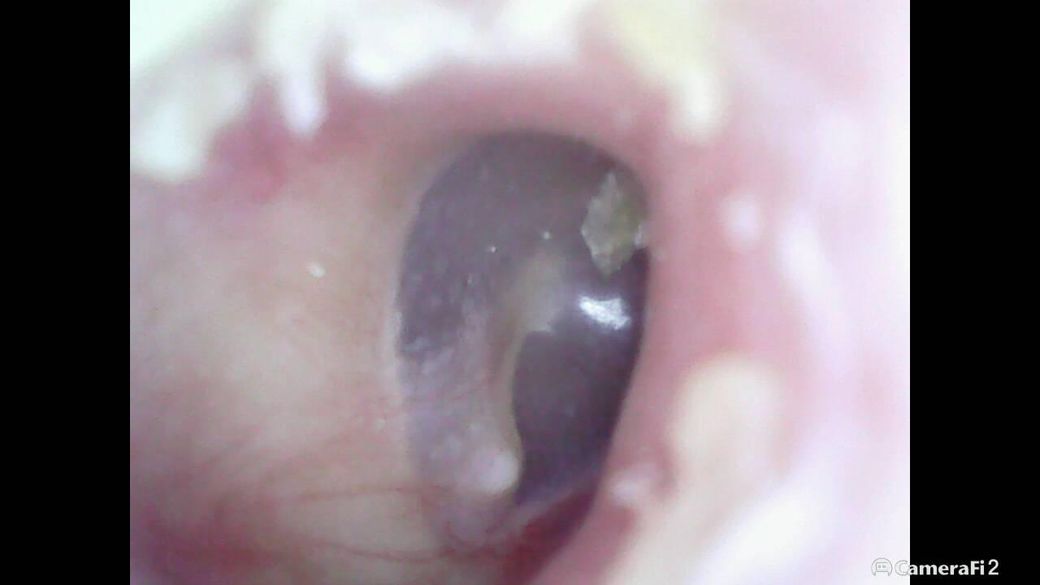

귀가좀 먹먹한거같아서 내시경으로 봤는뎆 고막에 흰색 무늬 점(?)같은게여러개 있는데 이거 정상적인건가요? 아님 무슨 문제가생긴건가요

• 1번 째 사진

• 괜찮고요. 고막을 의사가 볼때는 cone of light, 망치뼈, 삼출물과 천공 등 여부를 위주로 봅니다. 말씀해주신 부분은 큰 의미없구요.

사진 해상도가 제한적이지만 보이는 범위에서는 고막 전체 형태가 유지되어 있고, 천공이나 심한 발적, 팽륜 같은 급성 이상 소견은 뚜렷하지 않습니다. 말씀하신 흰색 점처럼 보이는 부분은 고막의 정상적인 반사(빛 반사), 각질 또는 건조한 분비물이 붙어 보이는 경우가 흔하며, 단순 중이염에서 보이는 고름이나 심한 혼탁과는 양상이 다릅니다.

다만 “먹먹함” 증상이 있다는 점은 별도로 해석해야 합니다. 이는 고막 자체 문제보다 이관 기능 저하(코막힘, 감기, 비염 등으로 중이 압력 조절이 안 되는 상태)에서 더 흔합니다. 이 경우 고막은 겉보기엔 정상에 가까워도 내부 압력 변화로 불편감이 생깁니다.

현재 단계에서는 급성 위험 소견은 낮아 보이며, 코막힘 관리, 하품·침 삼키기 등으로 이관을 열어주는 것이 도움이 됩니다. 다만 먹먹함이 1주 이상 지속되거나, 통증·청력 저하·이명 등이 동반되면 이비인후과에서 고막 상태와 중이 압력을 정식으로 확인하는 것이 필요합니다.